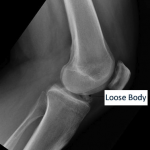

Articular cartilage damage can result in fragments of cartilage, which detach and exist as loose bodies within the knee. Loose bodies will often cause catching, locking and intermittent swelling of the knee. Knee arthroscopy can be done to remove painful cartilage flaps or loose bodies within the joint.

With the removal of a loose body a patient's recovery, weight bearing status and bracing will depend on additional surgical procedures performed or existing injuries. Most patients after knee arthroscopy are able to bear weight as tolerated without a brace.